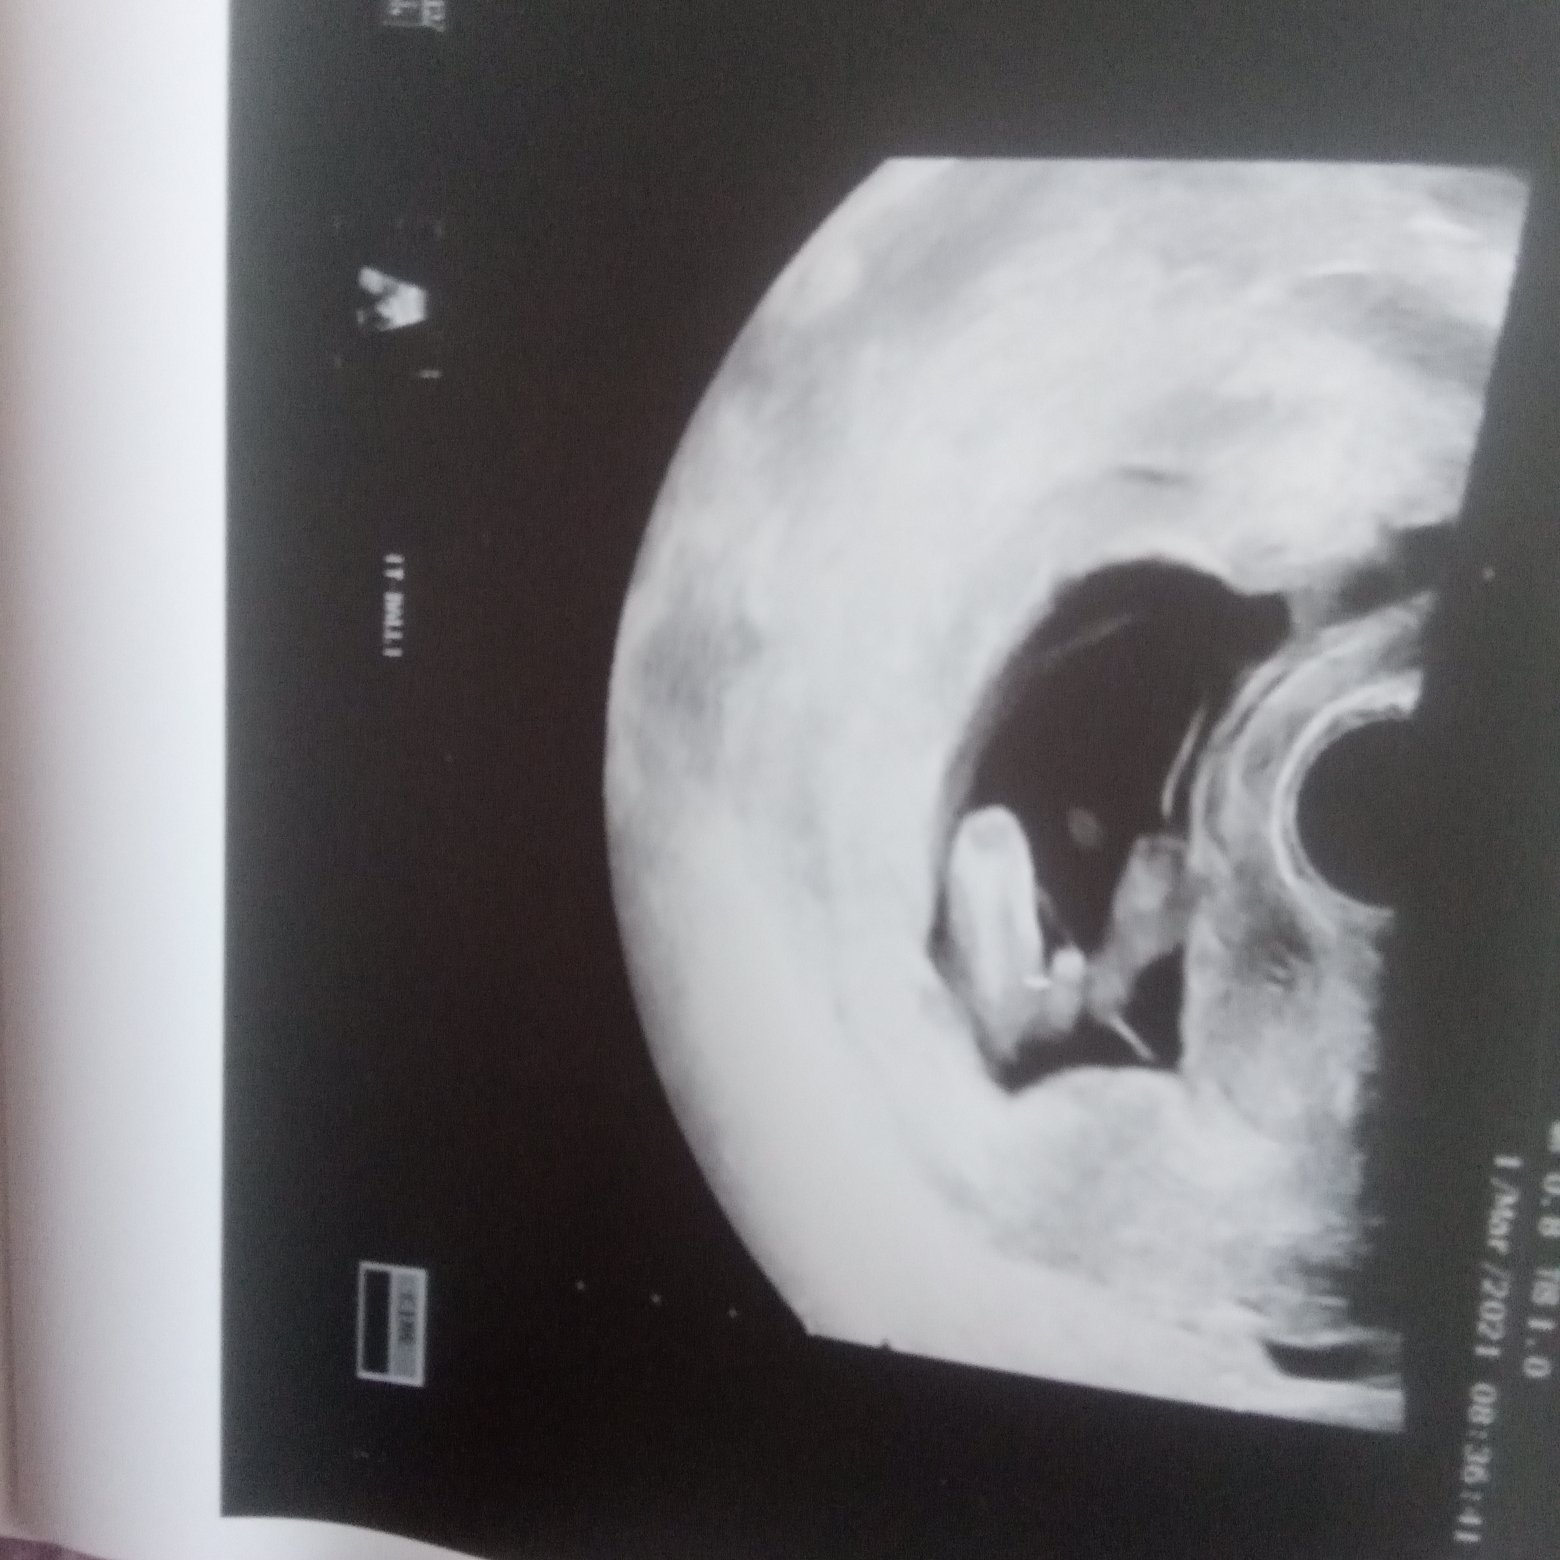

Usg chłopak czy dziewczynka

Witam w 19 tygodniu ciąży dowiedziałam się ze będę miała dziewczynkę w 20 tyg okazało się jednak , że to chłopak. Sama już nie wiem bo na jednym usg widać na pewno dziewuche a na drugim chłopca. Może to pempowina ?? Może ktoś mi pomoże rozwiązać ta zagadkę

Załączniki

• 4A8F5FF1-76CA-4DE0-AC12-5EDF08E820F2.jpg